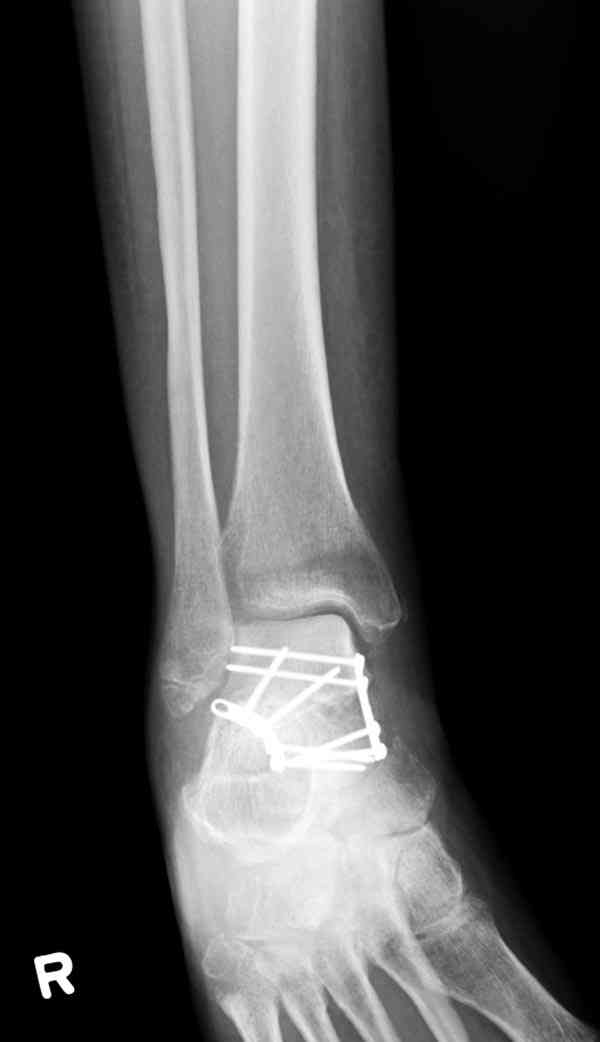

В вашем случае доступ через перелом медиальной лодыжки, обычный доступ через остеотомии лодыжки, где имеется возможность прямой репозиции тарана, после фиксации шурупами, лодыжки фиксируются обычным 2х лодыжечным методом.

Случай с множественным оскольчатым переломом тарана оперированный из двойного доступа.

Через 2 мес.: